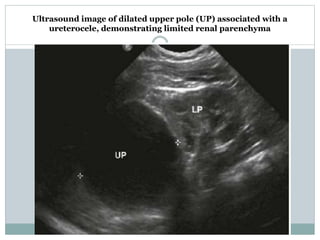

Ultrasound demonstrating dilated upper pole (UP) and lower pole (LP) associated with a

ureterocele. The upper pole has evident renal parenchyma. The lower pole is dilated because of

compression of the dilated upper pole ureter on the lower pole system, creating a partial obstruction.

Ultrasound image of dilated upper pole (UP) associated with a

ureterocele, demonstrating limited renal parenchyma